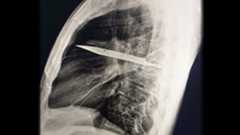

Instead, it appears that the talented Italian artist — who had a reputation for gambling, drinking, sleeping with prostitutes and even murder — died of a sword wound that developed a nasty infection,leading to deadly condition called sepsis, a new study finds. Sepsis is the body's overwhelming and life-threatening response to an infection.

After killing a rival in a sword fight, Caravaggio ran from the law and tried to repair his reputation, but to no avail. After more brawls, the last in which he was gravely injured, he died while traveling back to Rome, and was buried in a cemetery inPorte Ercole, Tuscany, according to the study and The National Gallery.

Satisfied they had Caravaggio's remains, the researchers next analyzed his teeth and found the bacteriaStaphylococcus aureus hiding within the remaining blood vessels of the artist's teeth. This bacterial infection likely led to Caravaggio's sepsis, the researchers said.

"[The cause of death] resulted from sepsis secondary to superinfection of wounds after a fight in Naples, a few days before the onset of symptoms," they wrote in the study.